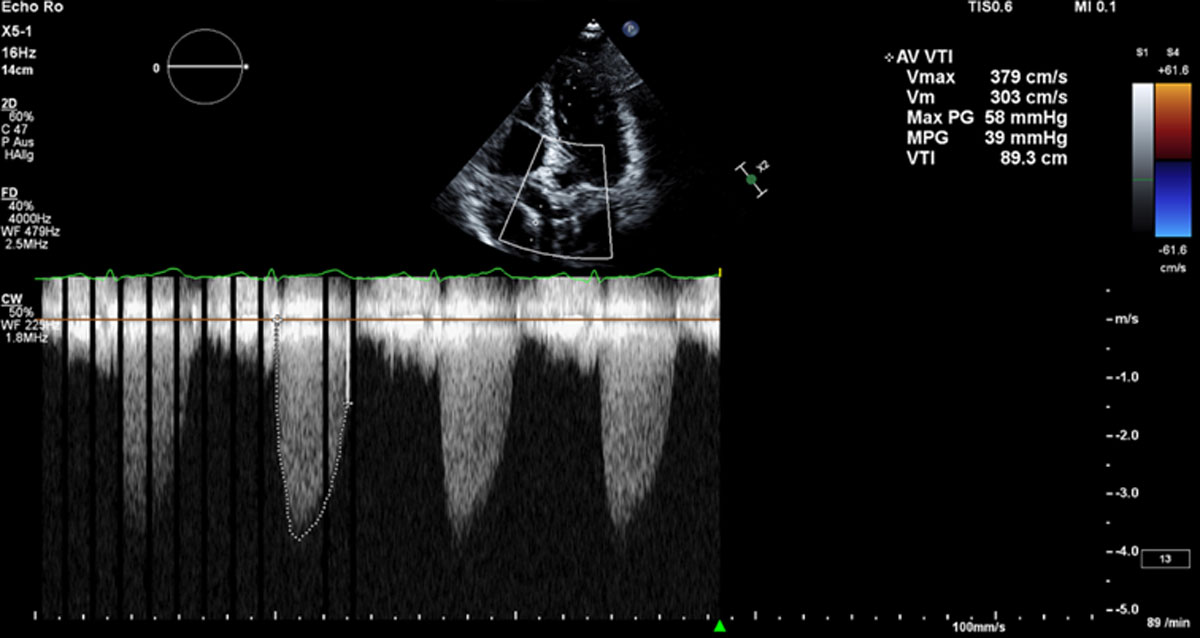

Eine 85-jährige Patientin wurde zur Untersuchung einer Aortenklappenstenose aufgenommen. Sie litt seit sechs Monaten unter Belastungsdyspnoe (NYHA-Klasse III) und Angina pectoris (CCS-Klasse II). Sie lebte mit ihrem Ehemann selbstständig in ihrer eigenen Wohnung. In ihrer Anamnese waren eine in Remission befindliche Magenkrebserkrankung und Psoriasis dokumentiert. Sie wies mehrere Anzeichen von Gebrechlichkeit auf, darunter einen BMI von 19,2 kg/m², eine 5-Meter-Gehgeschwindigkeit von 9,8 Sekunden und eine durchschnittliche Griffkraft von 12,7 kg. Die Echokardiographie ergab eine normale linksventrikuläre Ejektionsfraktion und eine schwere paradoxe low-flow-low-gradient Aortenklappenstenose, mit einem mittleren Druckgradienten von 39 mmHg, einer Aortenklappenöffnungsfläche von 0,5 cm² und einem Schlagvolumenindex von 30 ml/m² (Abbildung 1, Videos 1 und 2).

Abbildung 1. Druckgradienten über der stenotischen Aortenklappe